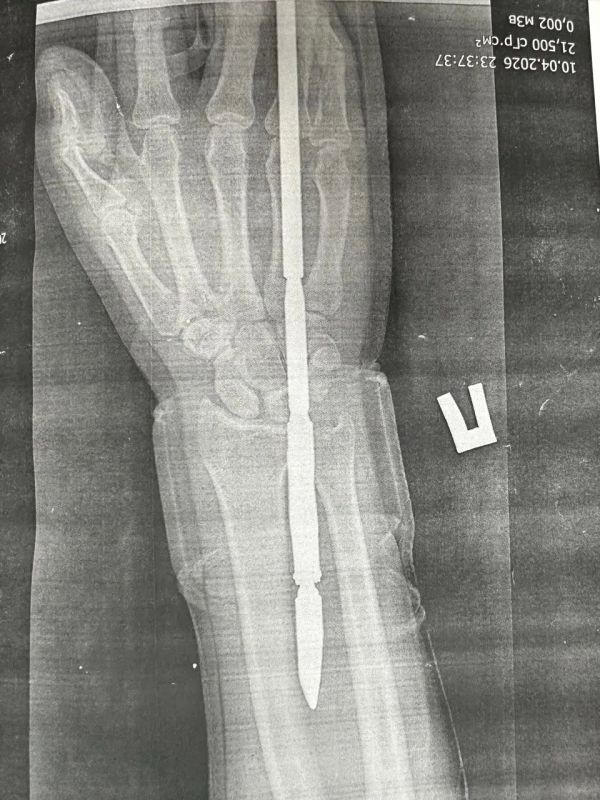

В отделение травматологии и ортопедии ГБ Орска поступил 29-летний мужчина, который загарпунил себя во время подводной охоты в Гайском округе. Гарпун с двумя зубцами прошёл между костями, не задев их.Врачи извлекли инородное тело, обработали рану и...